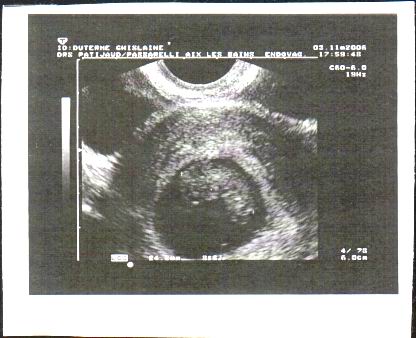

Voila mon reve le plus cher réaliser !!

eh oui je vais etre maman dans qques mois !!

je vous présente mon bébé !!

bisous à vous tous